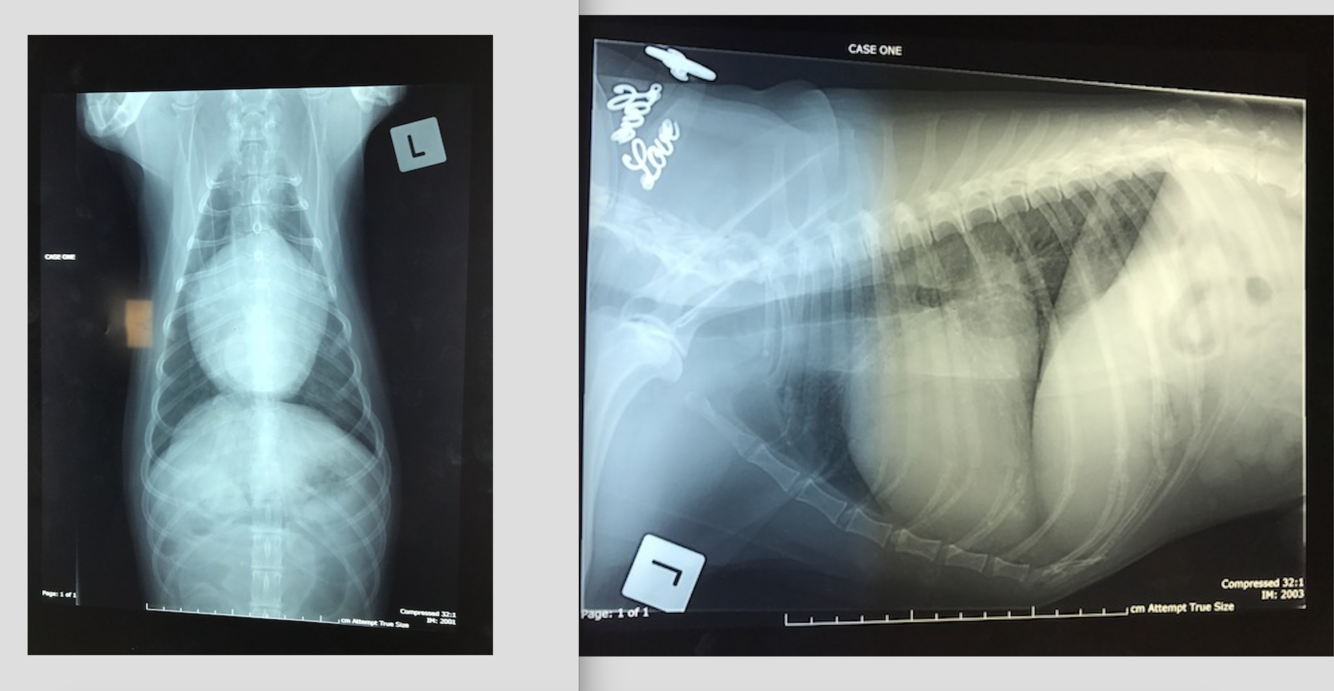

9 week old Male Labrador

Hx: Vomiting and anorexia for 2 days

HR 144 RR 36 Temp 39.7C NAD on abdo palpation

* Why decreased serosal detail?

* The gas within the GIT– which parts contain gas? Are the gas filled portions of the GIT over distended?

* The fluid filled portions– which parts contain fluid? Are they over distended?

* Which other organs can you ID? Are these within normal limits?

* What are your recommendations for further investigation and treatment of Baughie?